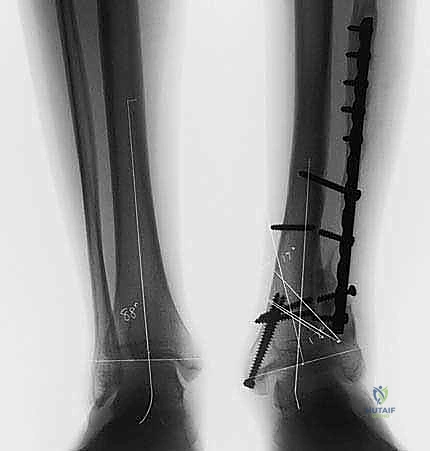

5. التثبيت الداخلي القوي (Internal Fixation)

بعد الوصول للزاوية المثالية التي تم حسابها مسبقاً، يتم تثبيت العظم بإحكام شديد باستخدام شرائح معدنية متطورة (Locking Plates) ومسامير من التيتانيوم. هذا التثبيت القوي هو ما يسمح للمريض ببدء الحركة والتأهيل مبكراً.

استخدام الشرائح والمسامير لتثبيت العظم

الأشعة السينية بعد التثبيت النهائي